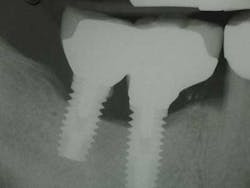

Fig. 1: Radiograph retained cement causing peri-implantitis.

Fig. 6: Radiograph reveals retained cement.